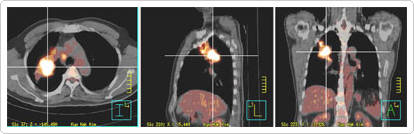

가장 걱정되는 부분이 폐라고 했더니 PETCT를 찍게 해주었다.

산정 특례 기간이라 5년간은 오늘 결제한 가격을 보니 PETCT 가격이 12,000원이었다

촬영 5분, 전후 휴식시간 1시간 이상 걸린 PETCT 촬영이었다.